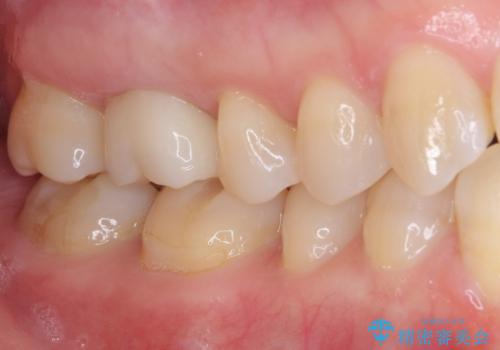

処置後、下顎の膿の出口はすぐに消えましたが、レントゲン写真からも分かるとおり、歯根途中に穴が開いており、充填材が歯根外にはみ出していました。数ヶ月経過を見たところ、特に異常は認められなかったため、補綴治療を行いました。